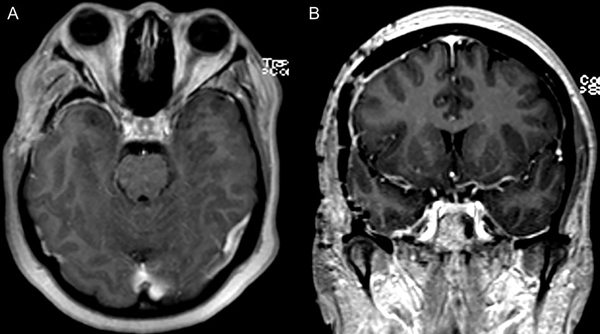

La anatomía patológica informó lesión compatible con pseudotumor inflamatorio. Realizó un mes de tratamiento con corticoides. Se realizó RMN de control a los 2 meses en la que se evidenció importante reducción del volumen de la lesión (Figura 2 y 3).

Figura 2. RMN de cerebro en secuencia T1 con contraste; cortes axial y coronal (A y B). Control a los 2 meses posterior a la cirugía y corticoterapia.